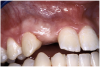

Periapical radiographs were taken to help determine the mesial-distal inclinations of the adjacent tooth roots (Figure 1). The radiographs revealed a serious issue, convergent roots for the right canine and right central, which eliminated that area as a potential implant-receptor site. The space between the left central and canine teeth was minimal, although the roots were relatively parallel. Clinical examination (manual palpation of the root eminences superiorly to the vestibule on the right side) confirmed the root convergence (Figure 2A). The flat, wide zone of the keratinized tissue and lack of interdental papilla was evident for the missing right lateral incisor. There was a marked difference in clinical appearance for the left lateral, which could impact the eventual plan of treatment (Figure 2B). Other significant clinical findings included bilateral facial bone concavities, which existed as a result of the congenitally missing tooth roots. As a diagnostic cue to the underlying bone topography, it is important to follow the demarcation between attached and unattached gingival tissue, and note the crestal width of the available keratinized tissue (Figure 2C).

Figure 2a  Pretreatment buccal views showed (A) root convergence, (B) a difference in clinical appearance of the left lateral, and (C) significant crestal width of keratinized tissue.

Figure 2a